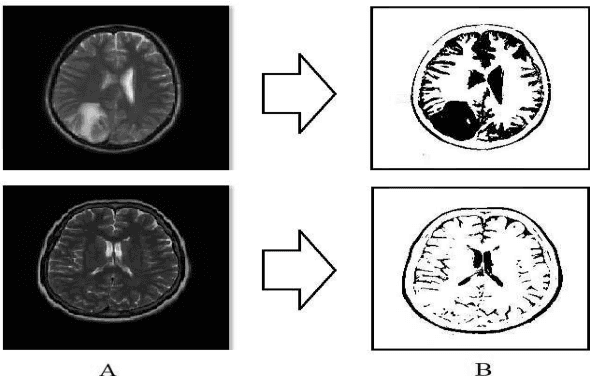

Abstract:Brain tumors pose a significant global health challenge due to their high prevalence and mortality rates across all age groups. Detecting brain tumors at an early stage is crucial for effective treatment and patient outcomes. This study presents a comprehensive investigation into the use of Convolutional Neural Networks (CNNs) for brain tumor detection using Magnetic Resonance Imaging (MRI) images. The dataset, consisting of MRI scans from both healthy individuals and patients with brain tumors, was processed and fed into the CNN architecture. The SoftMax Fully Connected layer was employed to classify the images, achieving an accuracy of 98%. To evaluate the CNN's performance, two other classifiers, Radial Basis Function (RBF) and Decision Tree (DT), were utilized, yielding accuracy rates of 98.24% and 95.64%, respectively. The study also introduced a clustering method for feature extraction, improving CNN's accuracy. Sensitivity, Specificity, and Precision were employed alongside accuracy to comprehensively evaluate the network's performance. Notably, the SoftMax classifier demonstrated the highest accuracy among the categorizers, achieving 99.52% accuracy on test data. The presented research contributes to the growing field of deep learning in medical image analysis. The combination of CNNs and MRI data offers a promising tool for accurately detecting brain tumors, with potential implications for early diagnosis and improved patient care.